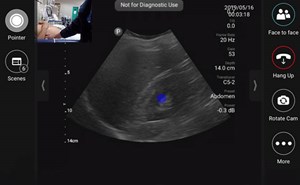

Sound Waves & Sirens: Creating a SonOlympics for EMS Teams Without Prior Ultrasound Training

As a new and enthusiastic member of the ACEP Prehospital, Austere, and Tactical Ultrasound Subcommittee, I’m thrilled to contribute to our mission of expanding the use of ultrasound in prehospital a...